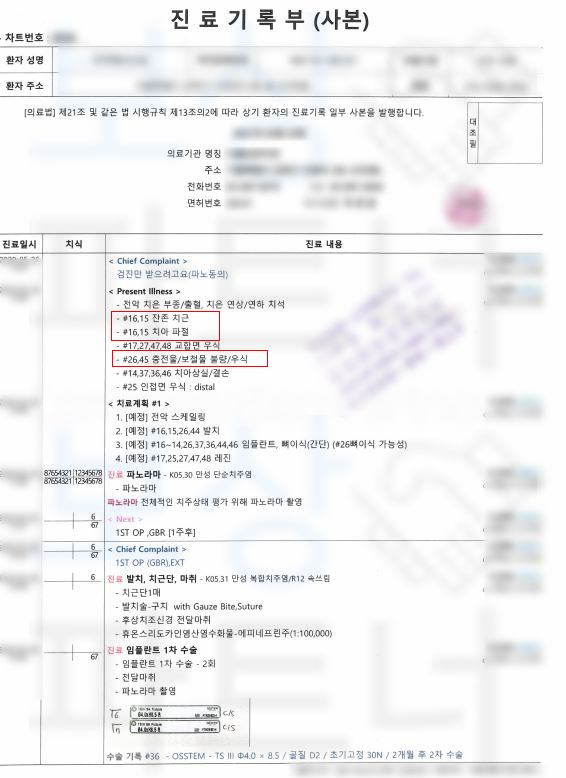

보상파트너는 의뢰인의 진료차트, 치아 파노라마 사진을 받아 분석을 진행하였고 보험금 지급의 가능성을 확인하였습니다. 보상파트너는 의뢰인의 임플란트 보험금 지급의 타당성을 증명하기 위해

의뢰인의 치아에 대해 K02.2 시멘트질의 우식증 K04.4 치수기원의 급성 근단 치주염 적용이라는 증거를 수집했고 약 2달간의 분쟁이 오간 결과 발치후 임플란트 보험금 인정 받을 수 있었습니다.